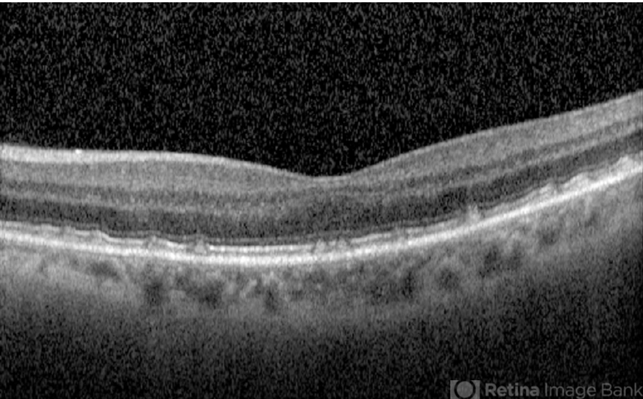

- subretinal, drusenoid deposit

- Subretinal drusenoid deposits.